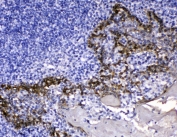

Cytokeratin 14, also known as cytokeratin-14 (CK-14) or keratin-14 (KRT14), is a member of the type I keratin family of intermediate filament proteins. In humans it is encoded by the KRT14 gene. This gene product, a type I keratin, is usually found as a heterotetramer with two keratin 5 molecules, a type II keratin. Mutations in the genes for these keratins are associated with epidermolysis bullosa simplex. At least one pseudogene has been identified at 17p12-p11.

Amino acids 446-472 (RQIRTKVMDVHDGKVVSTHEQVLRTKN-human) were used as the immunogen for the Cytokeratin 14 antibody.